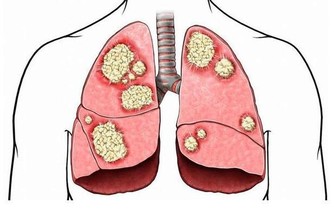

肺和呼吸系統負責維持幾種人體自然防禦機制。鼻子內部的纖毛會過濾你吸入的空氣。肺部也會分泌黏稠的液體,形成一道屏障,阻止細菌粘附肺部。想過著充實、快樂的生活,就得確保肺部健康。但是,我們每天都在呼吸過程中,接觸許多有害化學物質和污染物,會影響肺部健康,引發肺結核、百日咳、肺炎和支氣管炎等疾病。哮喘、慢性阻塞性肺病和肺癌等疾病也會對肺部造成長期影響。如果你想要改善肺部健康,可以按照下面的天然方法,幫助它們恢復最佳狀態。